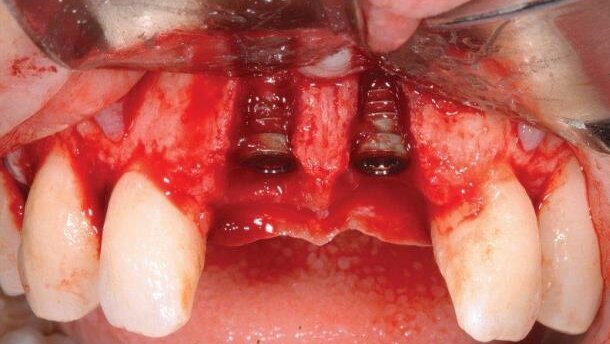

29-letnia pacjentka zgłosiła się z bólem siekaczy centralnych. Na zdjęciu radiologicznym zauważono zmiany okołowierzchołkowe. Plan leczenia zakładał ekstrakcję zębów z 5-tygodniowym okresem gojenia tkanek miękkich, implantację wczesną z jednoczasowym przeszczepem kości i tkanek miękkich oraz okres gojenia pozwalający na remodeling dziąsła. Po uzyskaniu zgody pacjenta, leczenie przebiegało następująco:

Autor prezentuje przypadek ekstrakcji z wczesną implantacją i jednoczasowym przeszczepem kości i tkanek miękkich.